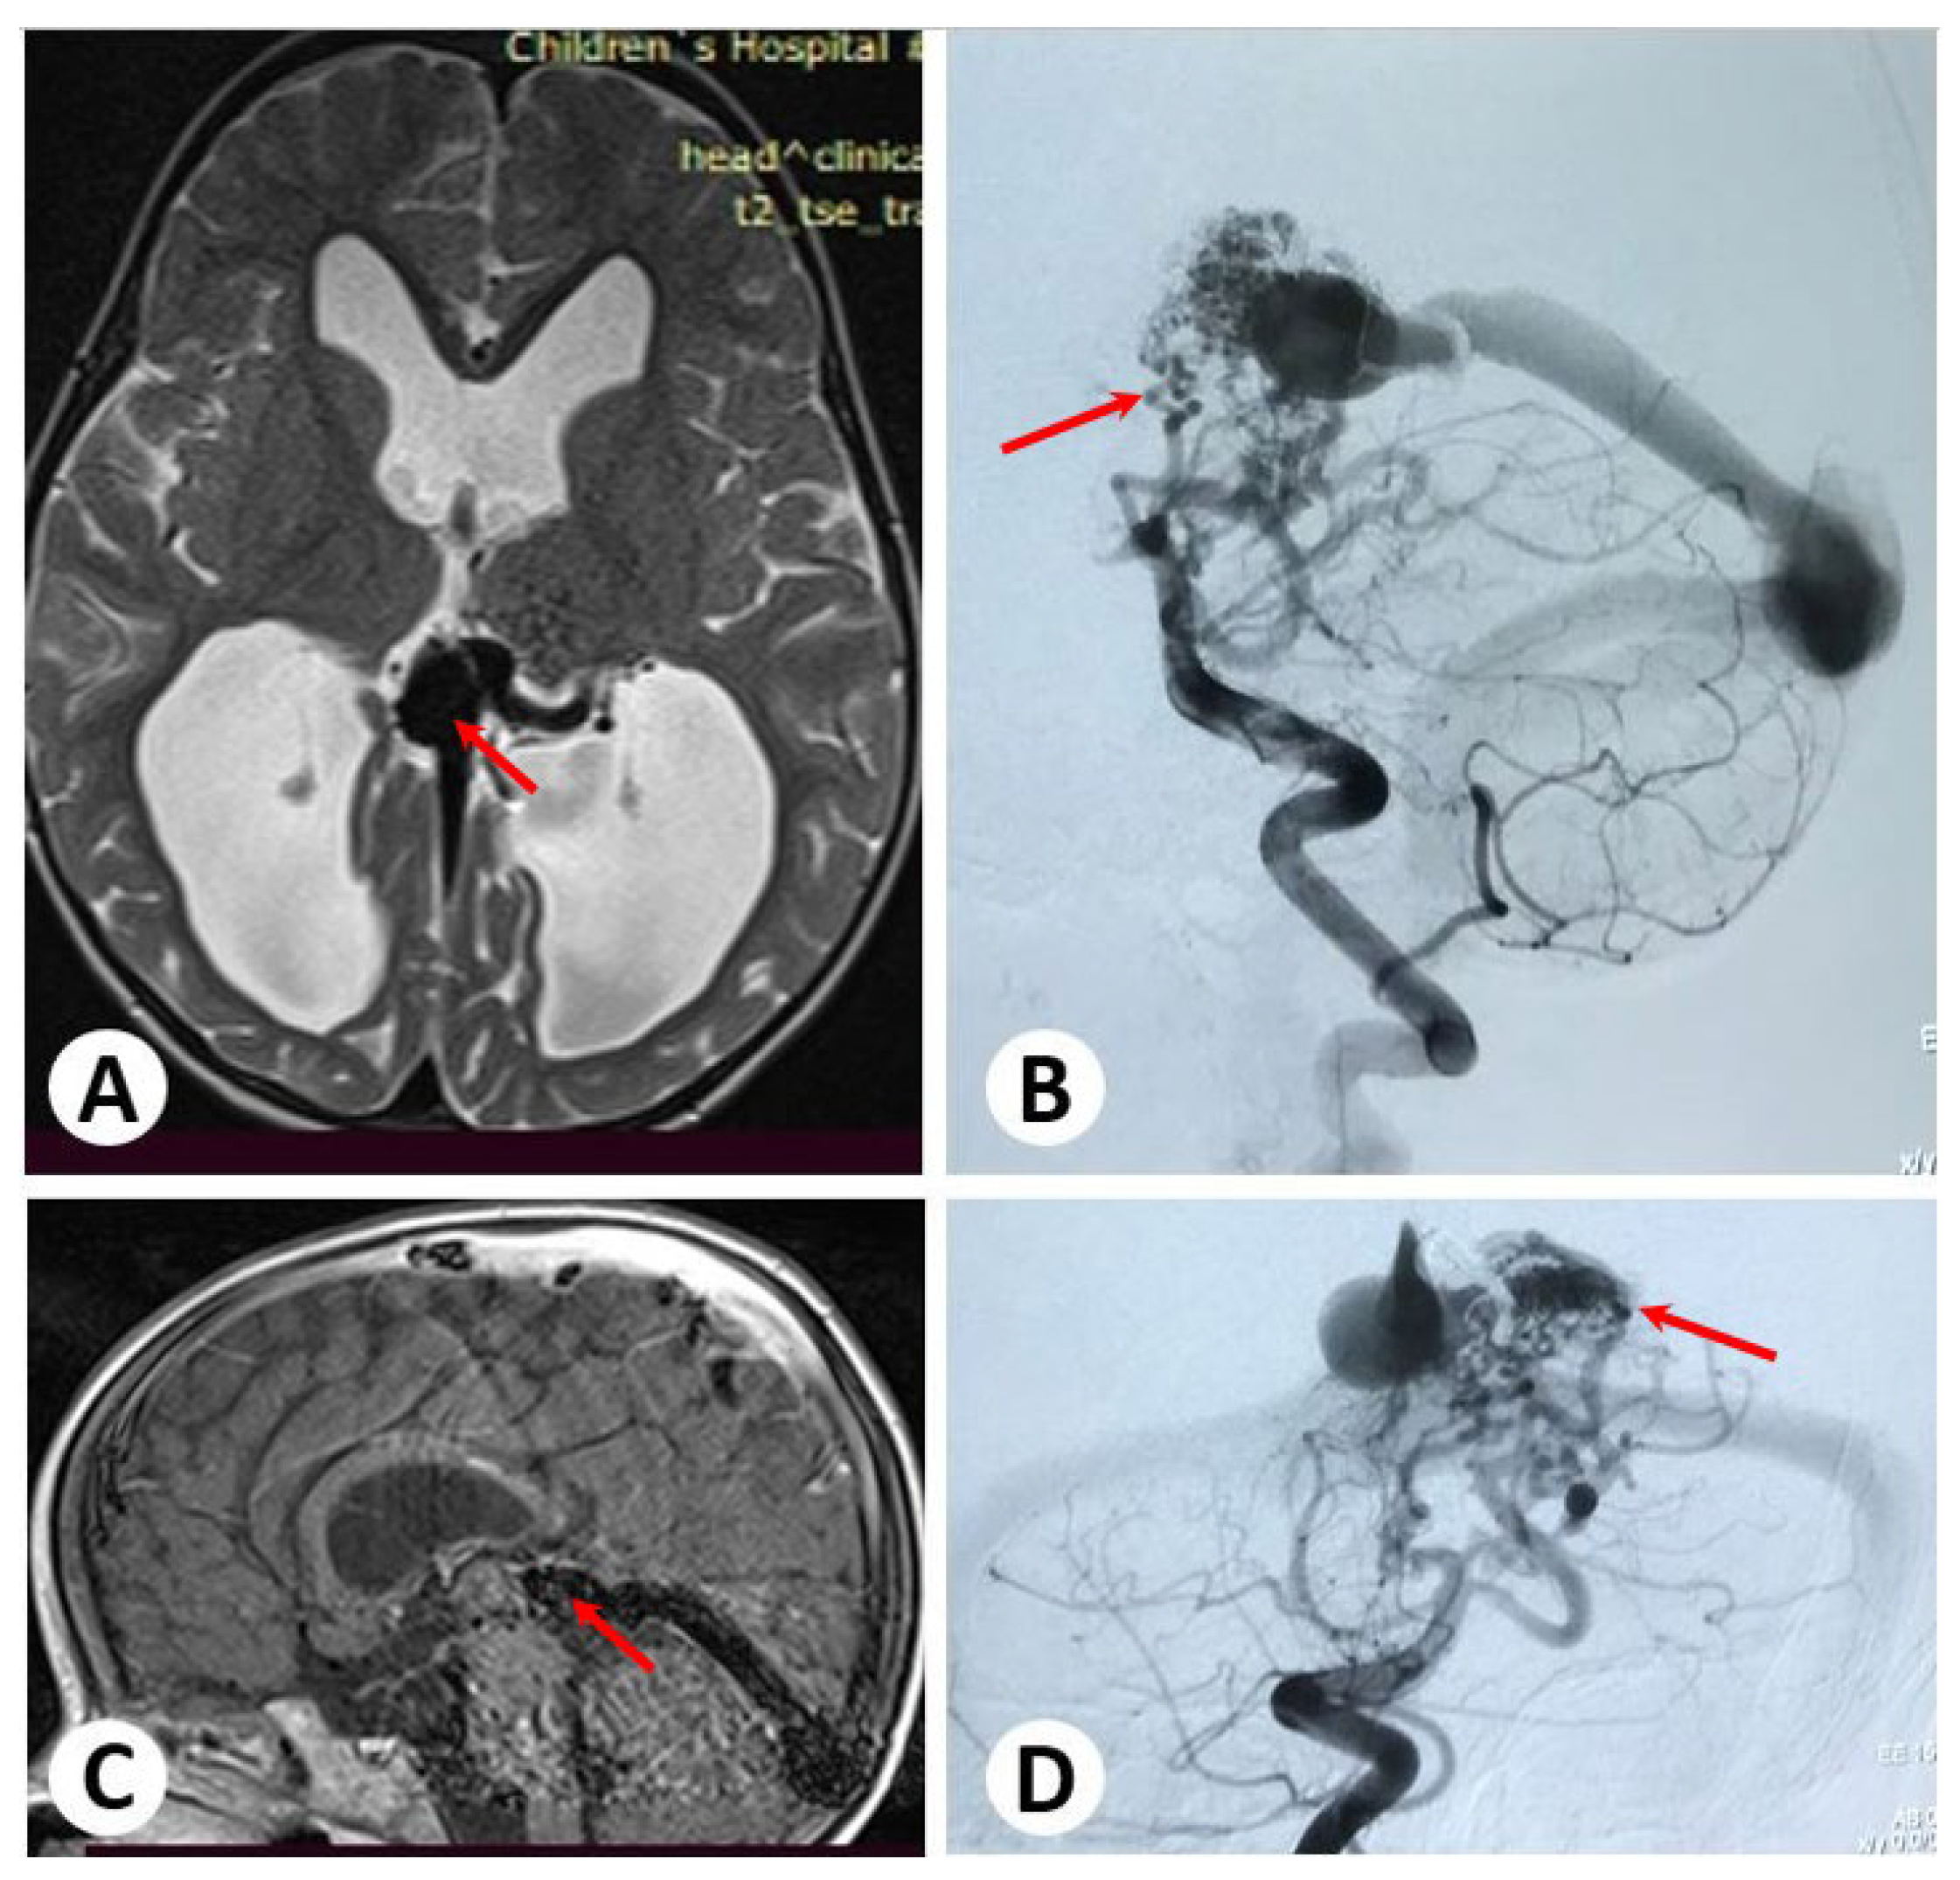

3.1. Illustrative Cases: Case 1